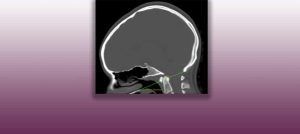

Institut Chiari & Siringomielia & Escoliosis de Barcelona is highly specialized neurosurgical center dedicated to the diagnosis and treatment of spinal and brain disorders, with a focus on the clinical concept of Filum Terminale Disease. Conditions treated include: